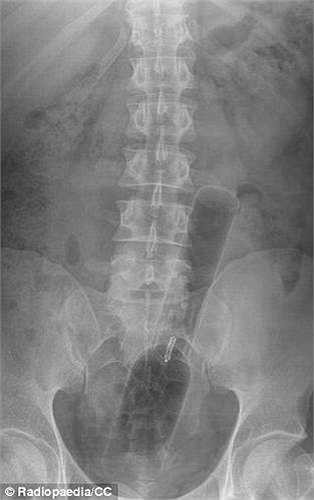

Bệnh nhân này trong khi quan hệ tình dục đã sử dụng đồ chơi tình dục tự chế bằng cách vặn một ống thuốc vitamin Berocca đặt lên đỉnh hộp xịt rồi cho nó vào trực tràng.